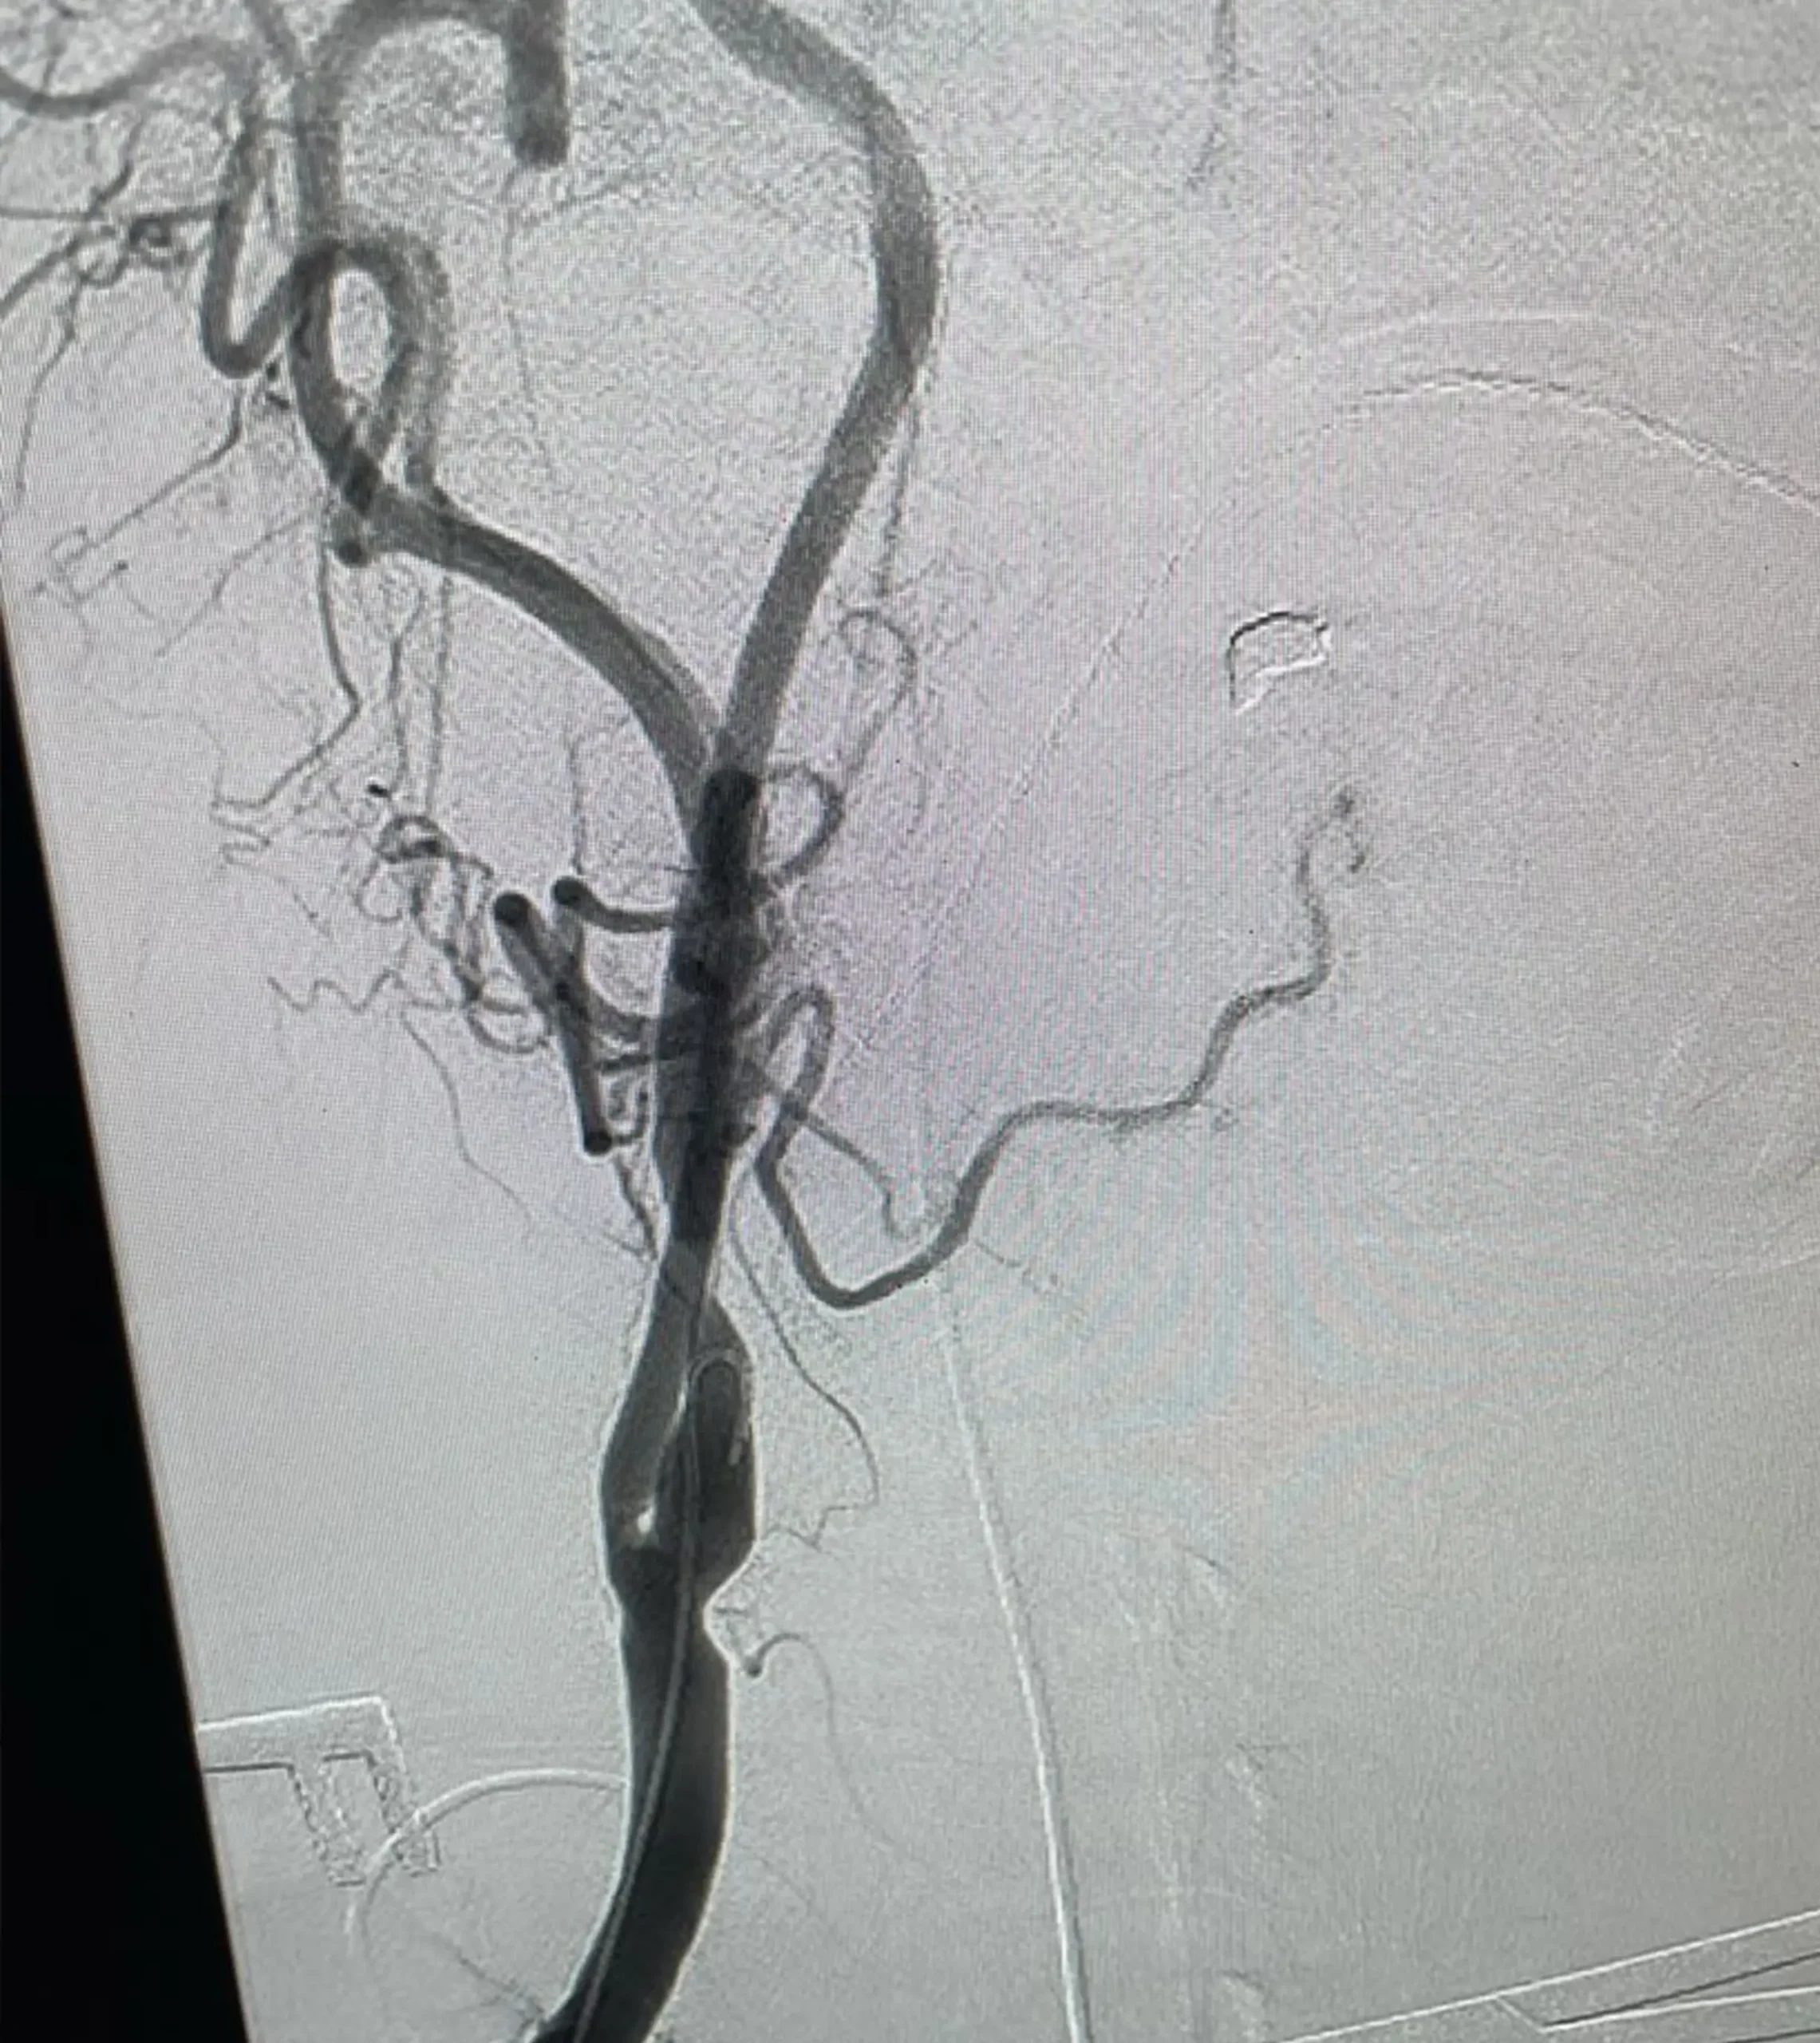

Dr. Akinrinlola is a highly skilled, board-certified vascular surgeon with extensive experience in both hospital-based and outpatient settings. Specializing in comprehensive vascular care, he has a particular focus on limb salvage, carotid interventions, peripheral interventions, dialysis access, and aneurysmal repair. His clinical expertise covers the full spectrum of vascular and endovascular procedures.